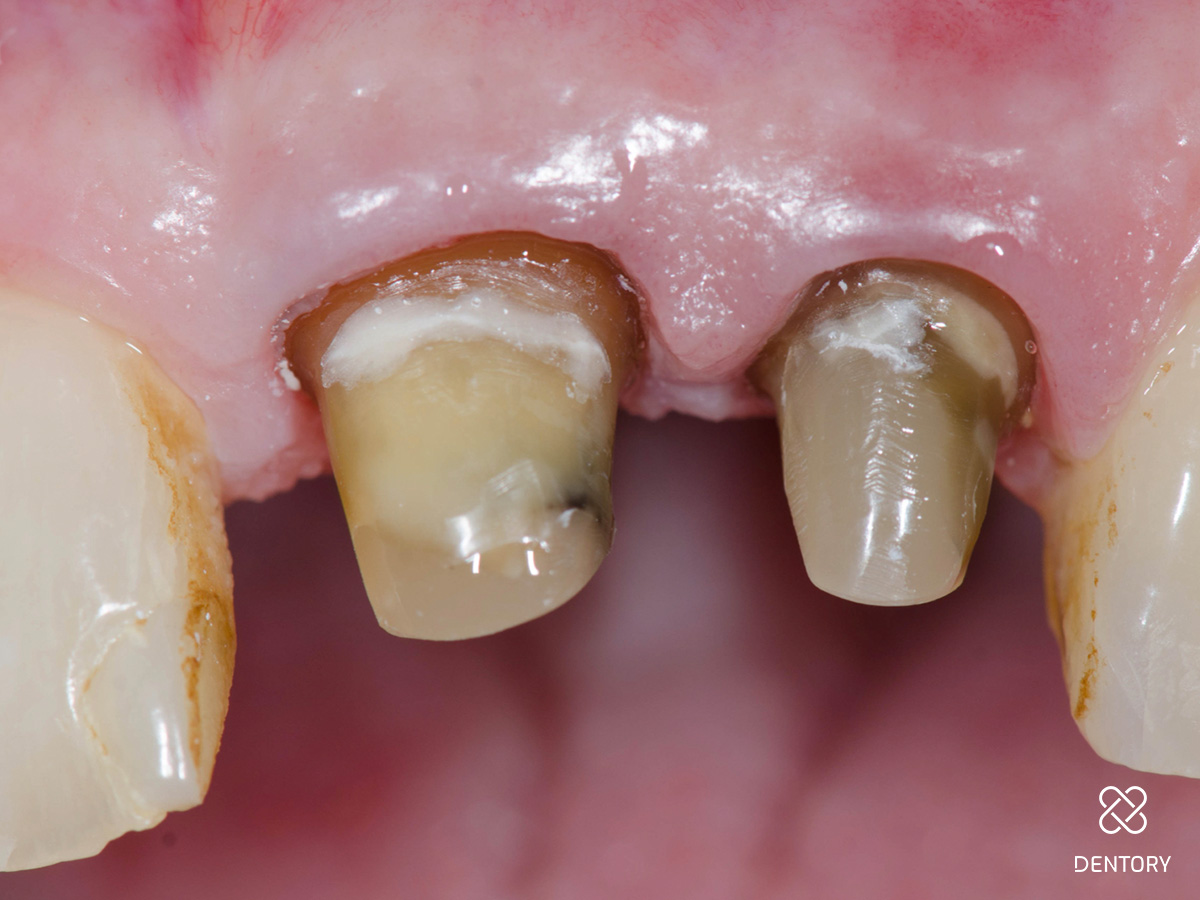

Abbildung 3

Kronenentfernung: Die Zähne waren wurzelkanalbehandelt und mit einem Stift versorgt. Das Bild zeigt die Situation nach Abnahme der Krone und Präparation der Stümpfe.